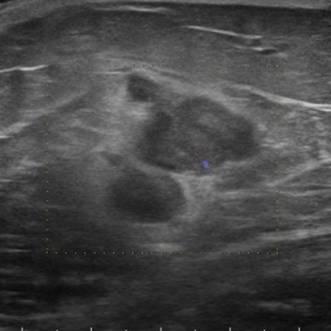

Di căn vú

Di căn vú - Ảnh 2

» Thông tin: Nữ giới – 70 tuổi.

» Lâm sàng: Khối tuyến vú / K hắc tố.